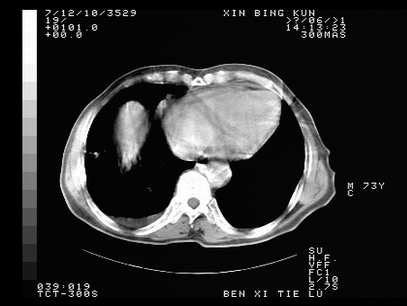

标题: CT10820:男,73岁,病史肺TB,现病史肺炎,直肠CA术后 [打印本页]

标题: CT10820:男,73岁,病史肺TB,现病史肺炎,直肠CA术后

1.两肺结核.2.两肺多发转移瘤.3右侧少量胸腔积液4.主动脉钙化.

双肺多发结节及条片状致密影,右侧少量胸腔积液。临床:直肠ca术后,肺tb病史。综合考虑:1 双肺转移!2 继发性肺结核合并感染!

两肺多发结节影,并见滋养动脉与其相连,考虑 两肺转移. 右侧胸腔积液考虑胸膜转移.

左肺上叶下叶背段,右肺中下叶见多发斑片状、条索状高密度影,兵变周围小结节影形成“树芽”样改变。 左肺上叶舌段近前胸壁处及右肺中叶内侧段见结节影。右侧胸膜腔内见液体密度区。纵隔内未见明确增大淋巴结。考虑左肺上叶舌段近前胸壁处及右肺中叶转移瘤可能性大。两肺继发型肺结核。右侧胸腔积液。

还有心包少量积液。